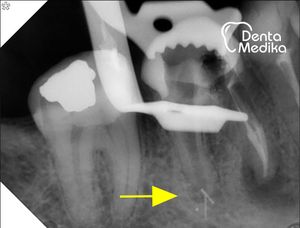

Více na: Reendodoncie - příklad 5